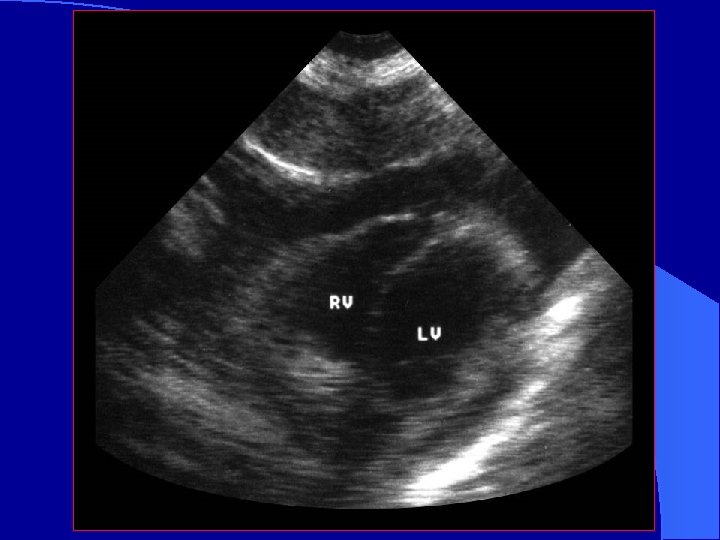

Blunt Cardiac Trauma l Basic Assessments – Pericardial effusion – Assess for wall motion abnormality – RV: l l closest to anterior chest wall Most likely to be injured l Advanced Assessments – Assess thoracic aorta – may need TEE to see all of thoracic aorta l l l Hematoma Intimal flap Abnormal contour – Valvular dysfunction or septal rupture

Blunt cardiac trauma l Injuries difficult to assess by FAST – Valvular incompetence – Myocardial rupture – Intracardiac thrombosis – Ventricular aneurysm – Coronary Thrombosis – Intra-cardiac Thrombosis